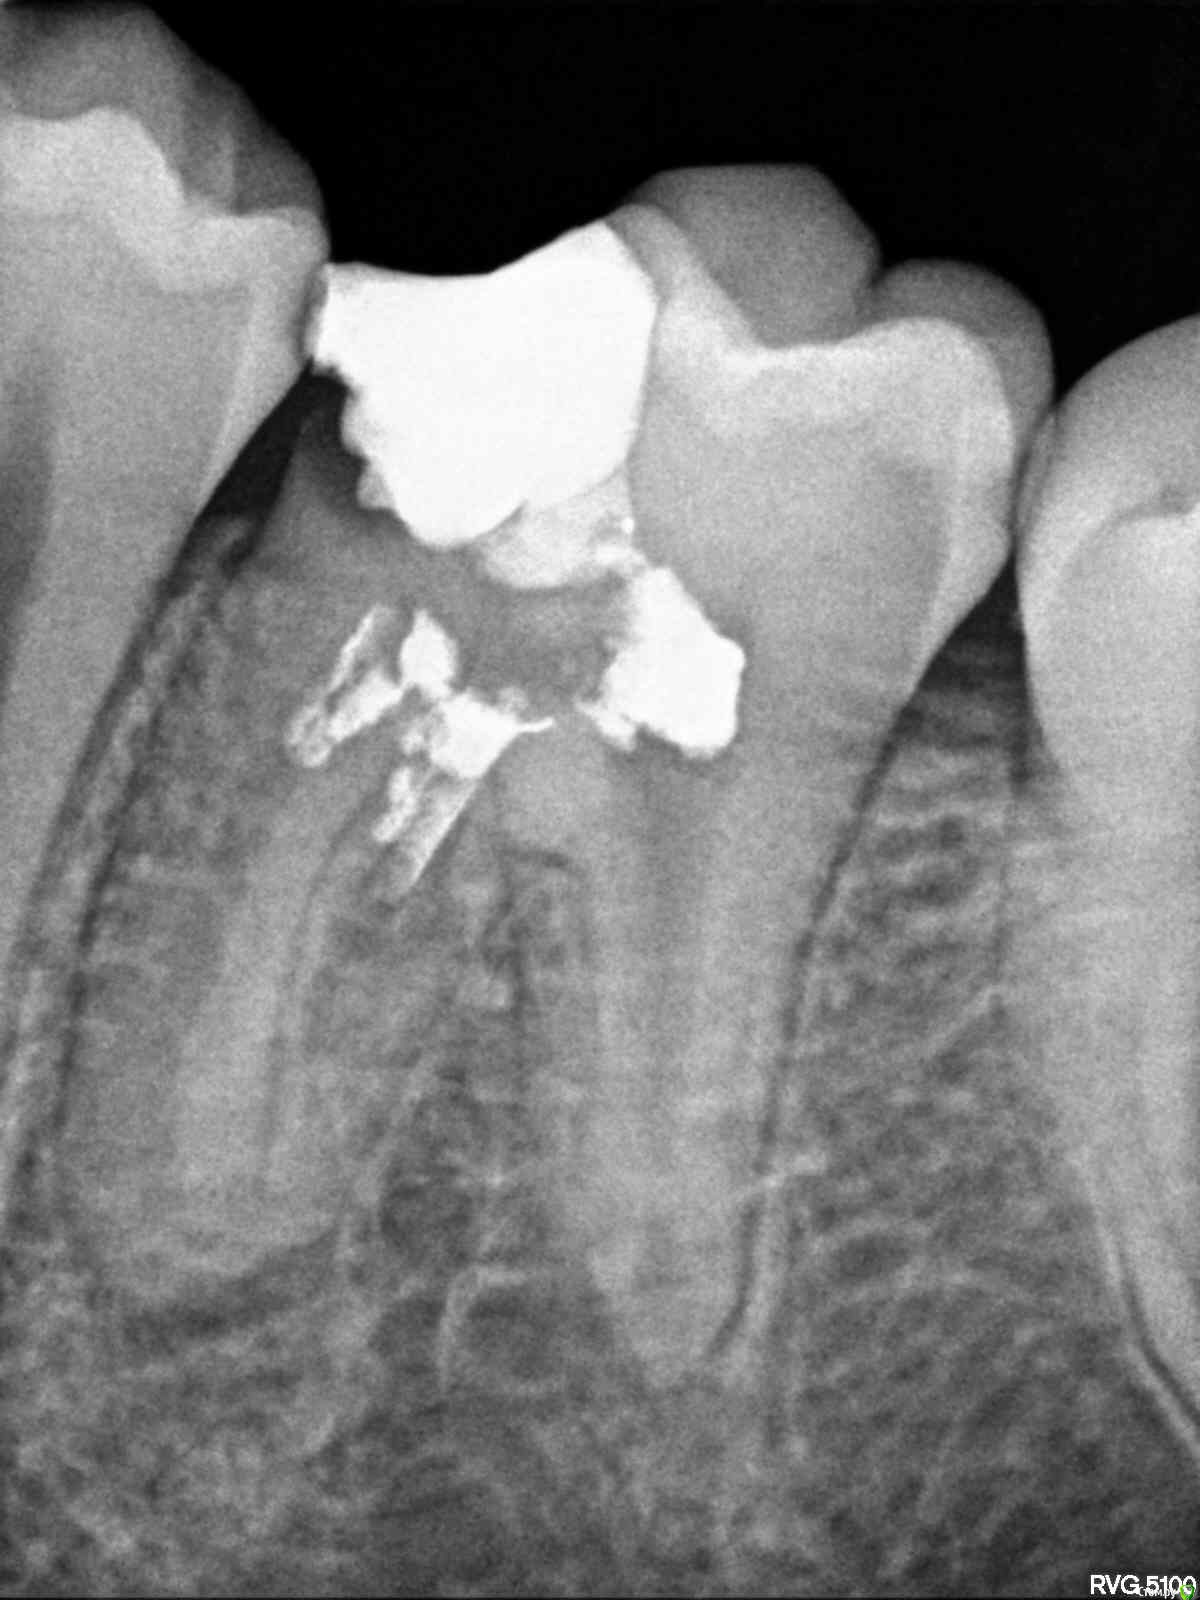

igorstom Опубликовано 10 декабря, 2016 Автор Поделиться Опубликовано 10 декабря, 2016 2013 год. Пациенту 13 лет. Зуб ранее лечен в ГСП. Зона роста нарушена, каналы пустые. Ссылка на комментарий